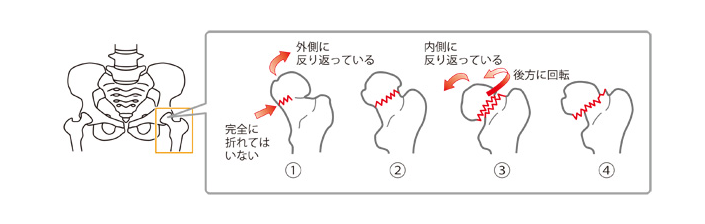

大腿骨頚部・転子部骨折の種類

大腿骨頚部骨折

大腿骨頚部骨折は、折れた骨の状態から4段階に分類されます。

4つの各段階の状態は、以下のとおりです。

出典:Mindsガイドラインライブラリ 大腿骨頚部/転子部骨折 Minds版やさしい解説

大腿骨頚部骨折の分類の詳細

| 非転移型 | ❶ もっとも軽度な骨折で、完全には折れておらず骨にひびが入っている状態 ❷ 骨は完全に折れてはいるが、折れた骨がずれたりしていない状態 |

|---|---|

| 転移型 | ❸ 折れた骨が少しずれ、折れた部分がぴったりと合わない状態 ❹ 折れた骨が大きくずれ、折れた部分がぴったりと合わない状態 |

出典:Mindsガイドラインライブラリ 大腿骨頚部/転子部骨折 Minds版やさしい解説

https://minds.jcqhc.or.jp/n/pub/3/pub0016/G0000622/0008